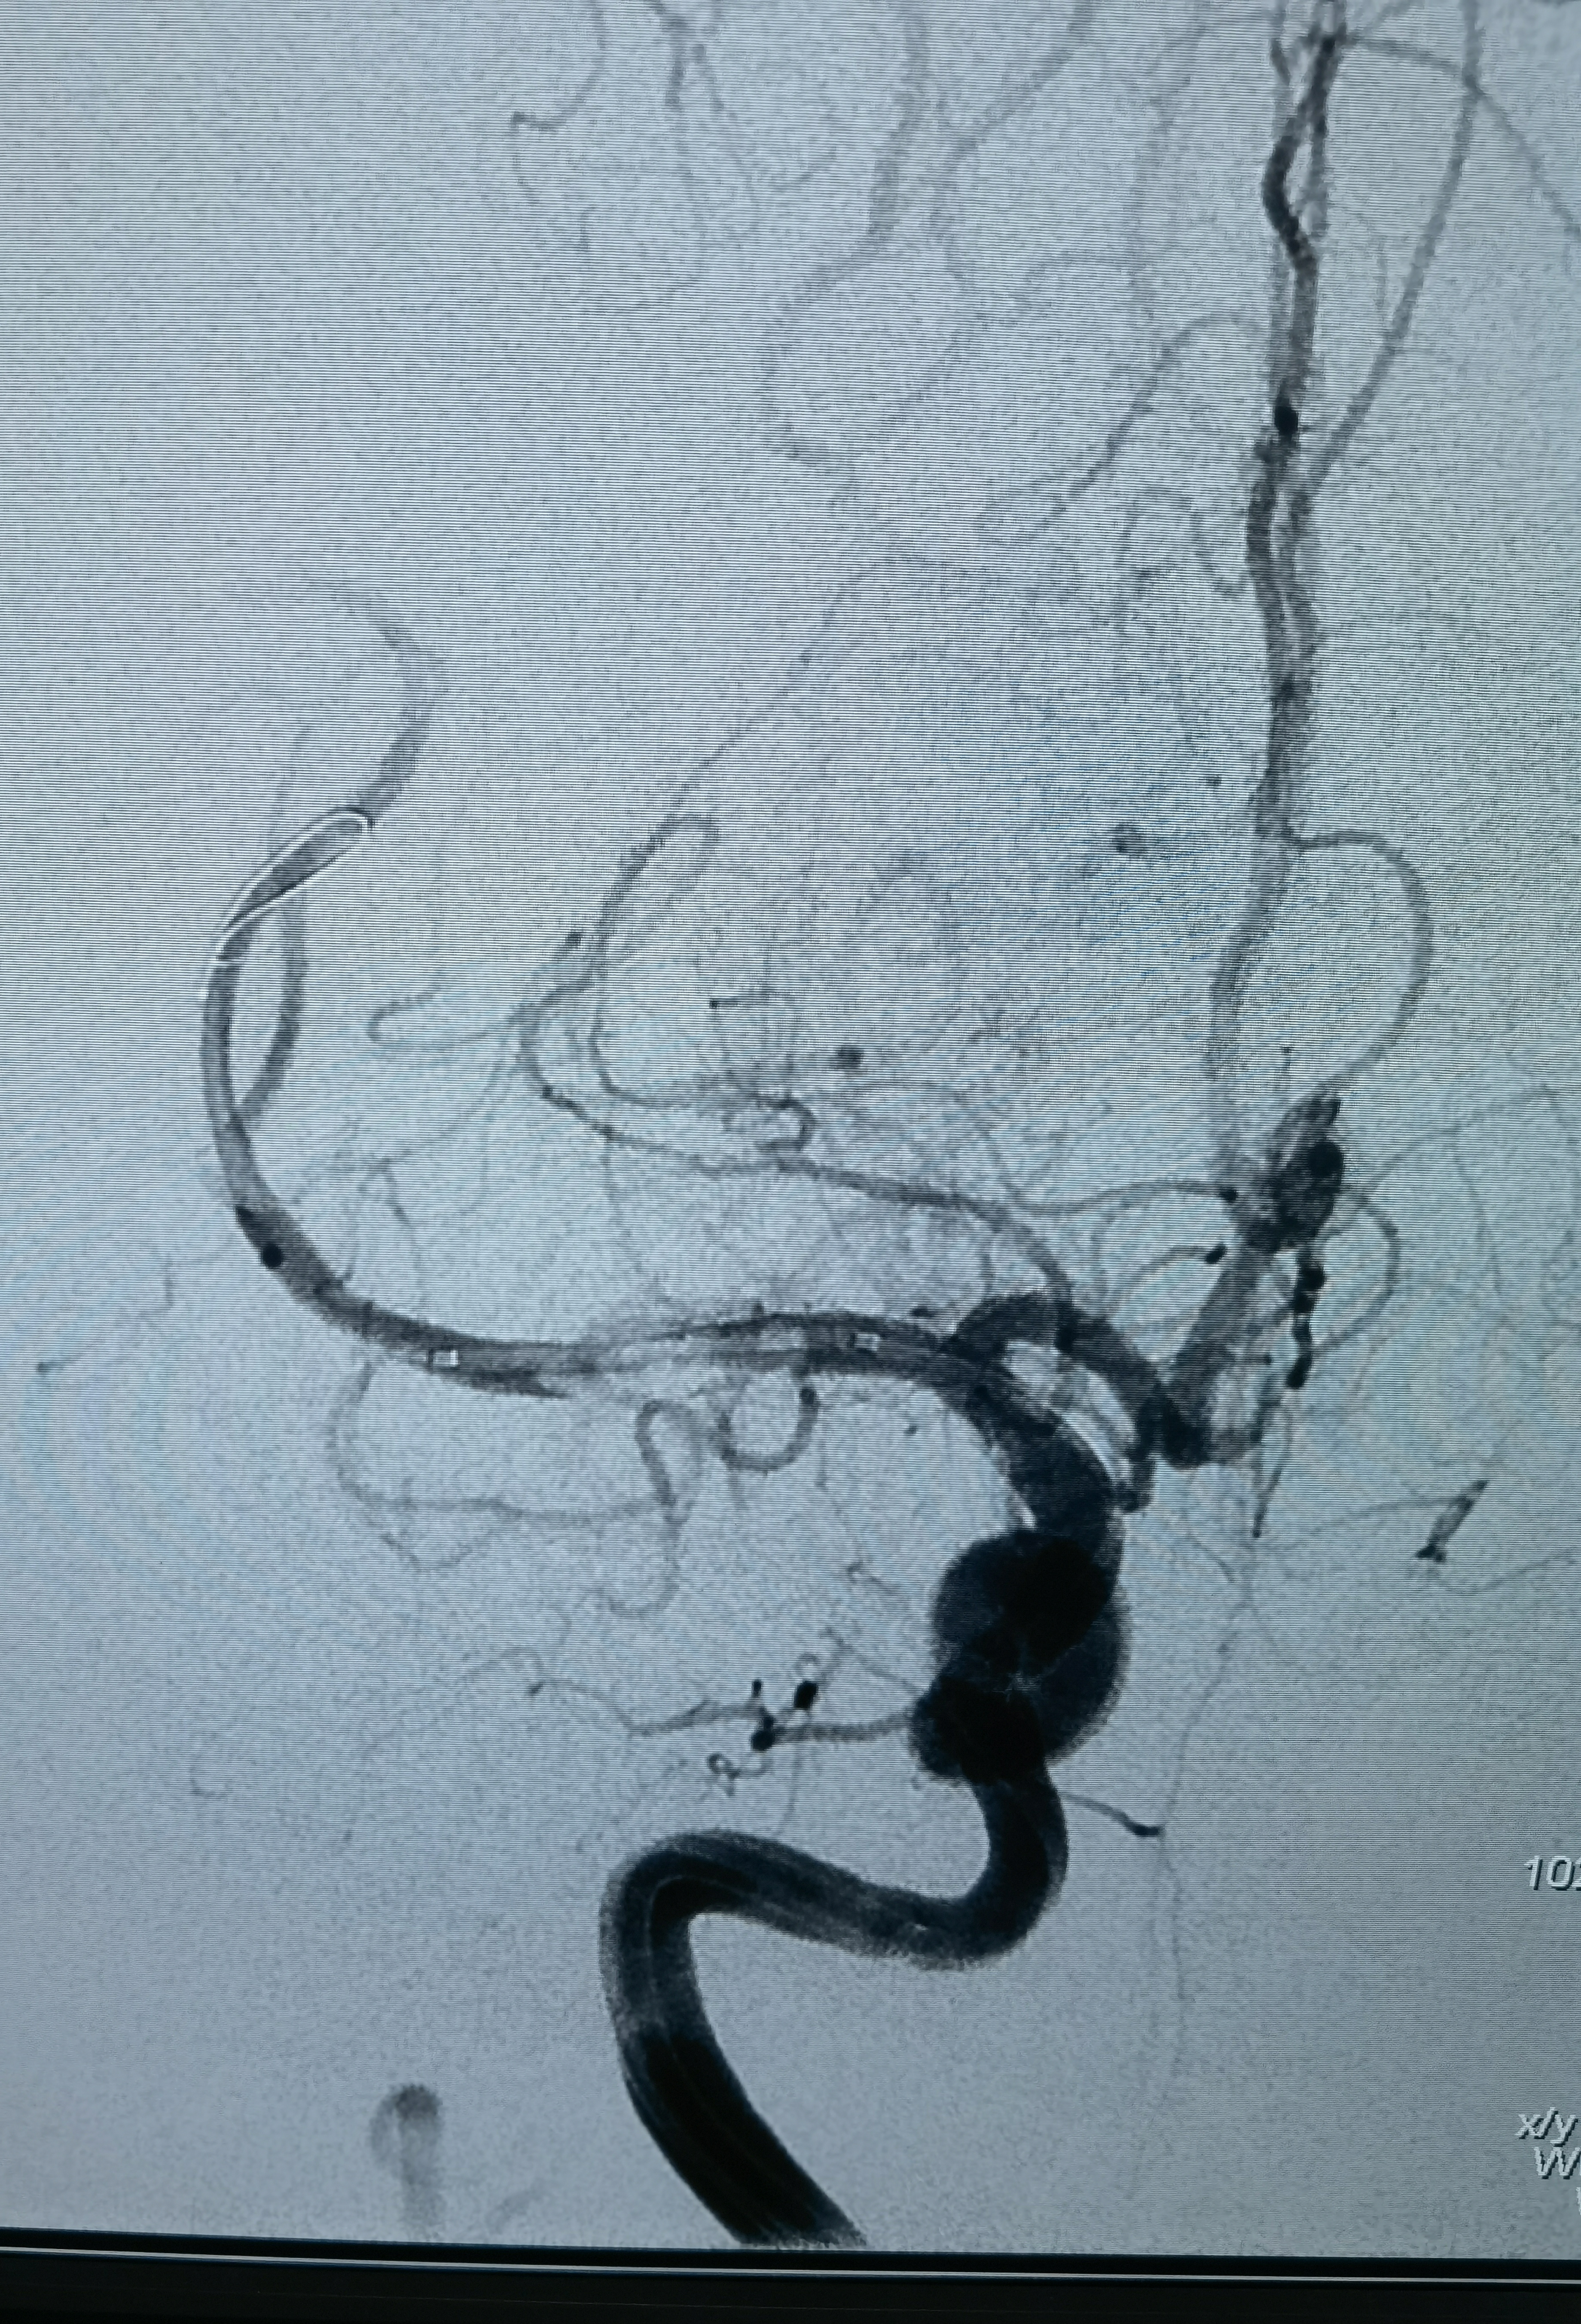

常规股动脉入路,穿刺时双侧股动脉搏动非常弱,两个人轮流尝试好几次才坚难穿刺右股动脉成功,置入股动脉鞘,造影确认在股动脉,但是发现股动脉比较细,没过多思考原因,直接泥鳅导丝带造影导管上去准备造影,结果发现到腹主动脉下端导丝导管过不去,造影发现腹主动脉近髂动脉处闭塞了!

用猪尾巴管再次造影确认腹主动脉确实闭塞了,这时明白为什么股动脉搏动弱不好穿刺了,赶紧换通路,穿刺右桡动脉!可是腹主动脉为什么闭了?紧急请心外科会诊,一打电话心外科说2018年在心外做瓣膜置换术时已经闭了,考虑大动脉炎!

这是术后在影像系统调出来2018年的CTA影像!当时腹主动脉下段已经闭塞了,通过肠系膜上动脉的侧枝以及双侧内乳动脉代偿供血!

改为右桡动脉入路,桡动脉搏动也弱,考虑大动脉炎可能右上肢血管也受影响了,不过还是穿刺成功,泥鳅导丝带猪尾巴管造影,在腋动脉处通过困难,试了两次还是顺利过去了,弓造影上可以看到右侧锁骨下动脉几乎不显影,肋颈干发出粗大分支血管向右上肢供血,说明锁骨下要么闭塞,要么也是重度狭窄,弓造影结束长泥鳅导丝保留,退出猪尾巴管,交换上SIM造影导管,在弓里成袢后超选右颈总困难,导管被血管抱死,导管软,内衬泥鳅导丝推不动!

换MPD头端放到头臂干右颈总开口处,内衬猪尾巴管,利用猪尾巴管头端的弯儿勾右颈总动脉,猪尾短,截了一节MPD,把泥鳅导丝头端送到右侧颈内动脉,猪尾巴管带到分叉,猪尾巴管造影确认右侧大脑中动脉闭塞!

闭塞血管明确,需要取栓治疗。问题来了!手头没有合适的6F经桡的中间导管,也没有合适的6F长鞘!怎么办?换8F鞘!鞘头进入血管一点,能固定住就行,泥鳅长单弯同轴带8F禾木的导引导管到右侧颈内动脉!

中间再上一禾木6F127抽吸导管,造影

先上抽吸导管抽吸一把,抽出一小块血栓!造影没有通!

上取栓支架取栓,还是没通!

第一支架取栓后造影!

再上取栓支架,这是取栓支架打开造影,能看见支架压缩影,提示有狭窄!

支架取栓两次没通,不敢过多用支架拉了,上球囊扩张两次,大脑中水平段扩一次,远端扩一次!

扩完血流恢复,血管通了,但是大脑中动脉M1仍有血栓,似乎还有点夹层,动脉给了10ml替罗非斑,观十余分钟,M1血栓又增加了,血流也变差,怎么办?想支架成型,但是患者有大动脉炎,不贴支架血流维持不住,术中商量一下考虑患者年轻,还是要尽量让患者降低瘫痪的机率,遂决定植入药物涂层支架,就算动脉炎引起支架内闭塞也需要一定时间,患者大脑前有通过软膜支向大脑中供血区代偿,到时候慢性闭塞可能患者不会出现严重影响!

药物涂层支架

支架植入后血流完成恢复!